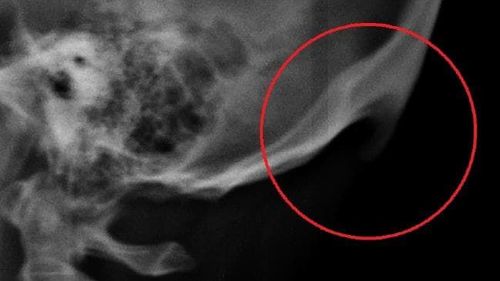

या युनिव्हर्सिटीने एक रिसर्च पेपर प्रसिद्ध केला आहे त्यात असा दावा करण्यात आला आहे, की जे मोबाईलवर तासनतास पडीक असतात. त्यातल्या त्यात ज्यांचे वय 18 ते 30 च्या दरम्यान आहे ते लोक या नविन प्रॉब्लम मध्ये अडकू शकतात. सनशाईन कोस्टच्या रिसर्सनुसार मोबाईलवर जास्त वेळ काम करणाऱ्या व्यक्तीच्या डोक्याच्या मागच्या भागात एक अणकुचीदार हाड वाढत असते. या अणकुचीदार हाडाला 'टेक्स्ट नेक' असे नाव देण्यात आले आहे. या हाडाचा आकार 2.6 सेमी पर्यंत असु शकतो. आणि हा फक्त दावा नाही मंडळी असे हजारो केसेस पुढे आलेल्या आहेत ज्यात स्पष्ट समजते की जे मोबाईलचा अतिवापर करतात त्यांच्या डोक्याच्या मागच्या भागात हाड वाढलेले आहे.

याचे कारण त्या रिसर्सने असे सांगितले की मोबाईलचा वापर करणारा व्यक्ती सहसा त्यात मान खुपसुन बसलेला असतो. त्यामुळे त्यांच्या डोक्याच्या मागच्या भागात हाड वाढते आणि शिंगाप्रमाणे दिसू लागते. याच्यावर एकंच उपाय आहे - मोबाईलचा वापर कमी करणे.